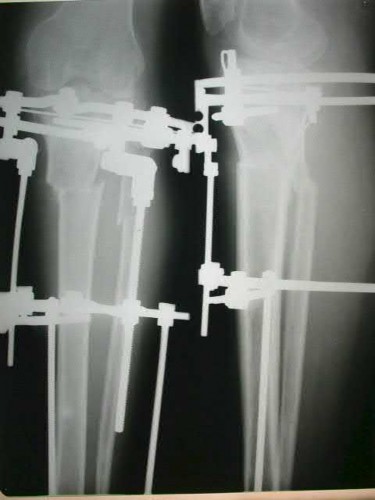

A 30-year-old male is involved in a motorcycle collision. Radiographs demonstrate a displaced symphysis pubis (3.5 cm) and widening of the left sacroiliac joint. He remains hypotensive despite 2 liters of crystalloid and 2 units of packed RBCs. A pelvic binder was properly placed in the field. What is the most appropriate next step in management?

Explanation

In a hemodynamically unstable patient with a pelvic ring injury, despite initial resuscitation and mechanical stabilization (pelvic binder), the immediate priority is hemorrhage control. This is best achieved via pre-peritoneal pelvic packing or angioembolization, depending on institutional protocol. CT is contraindicated in hemodynamically unstable patients.